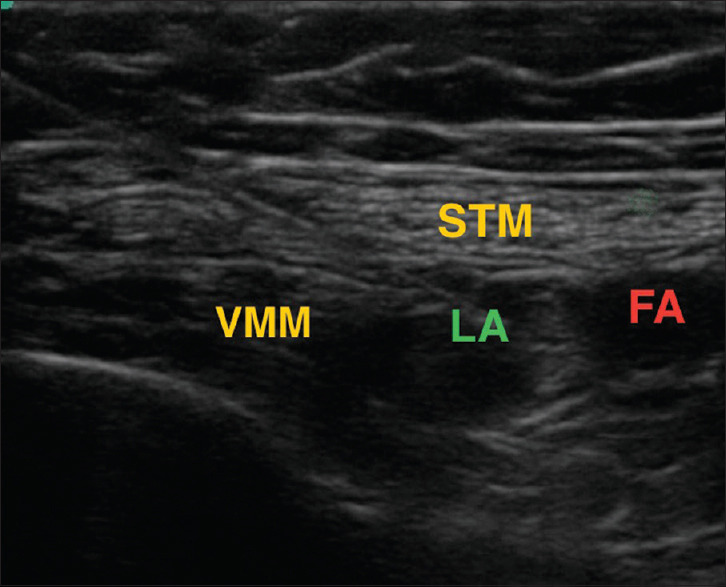

Material and methods: Sixty patients aged 18-80 years and ASA grade I-III undergoing unilateral TKA were randomised to two groups postoperatively to receive DSB or SSB. Patients in group DSB received distal femoral triangle block (15 ml) + proximal adductor canal block (20 ml), while group SSB received only proximal adductor canal block (20 ml). Primarily, the changes in pain intensity and pain control in terms of static and dynamic visual analogue score (VAS) with the duration of analgesia and cumulative dose requirement of rescue analgesic in the first 24 hours postoperatively were studied. Secondary outcomes were the postoperative degree of motor blockade, the ability of early ambulation, patient satisfaction and complications. Statistical analysis was done using the student t-test and Chi-square test using MedCalc version 12.4.3.0.